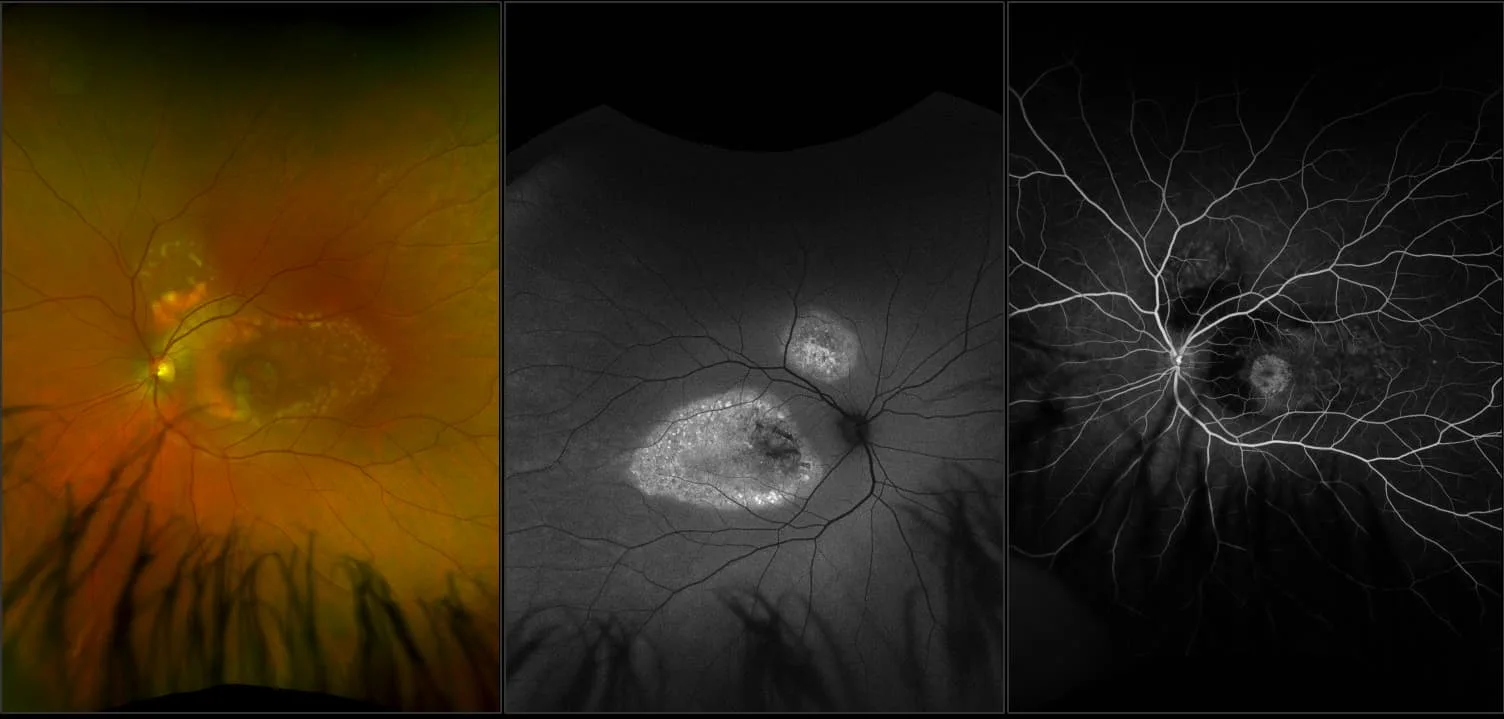

optomap® Recognizing Pathology

This material is designed as a searchable reference resource to support clinical decision-making. The information contained here should be used as general guidance when viewing optomap and OCT images from Optos devices. The differential diagnosis should be made under the direction of the responsible physician. These images were taken on the latest ultra-widefield optomap devices.

optomap Recognizing Pathology is searchable by pathology and/or optomap image modality. You may search by multiples of each selection. Each individual case is represented by the accompanying thumbnail image. Most cases include several different optomap image modalities. To view a full description of the case, please click on the thumbnail. Each image in the case will be made available through our OptosAdvance software which provides multi-dimensional visualization of digital images to aid in the analysis of anatomy and pathology. Support and pathology definitions can be found by selecting one of the buttons, above. Should you have questions, please complete the form below.